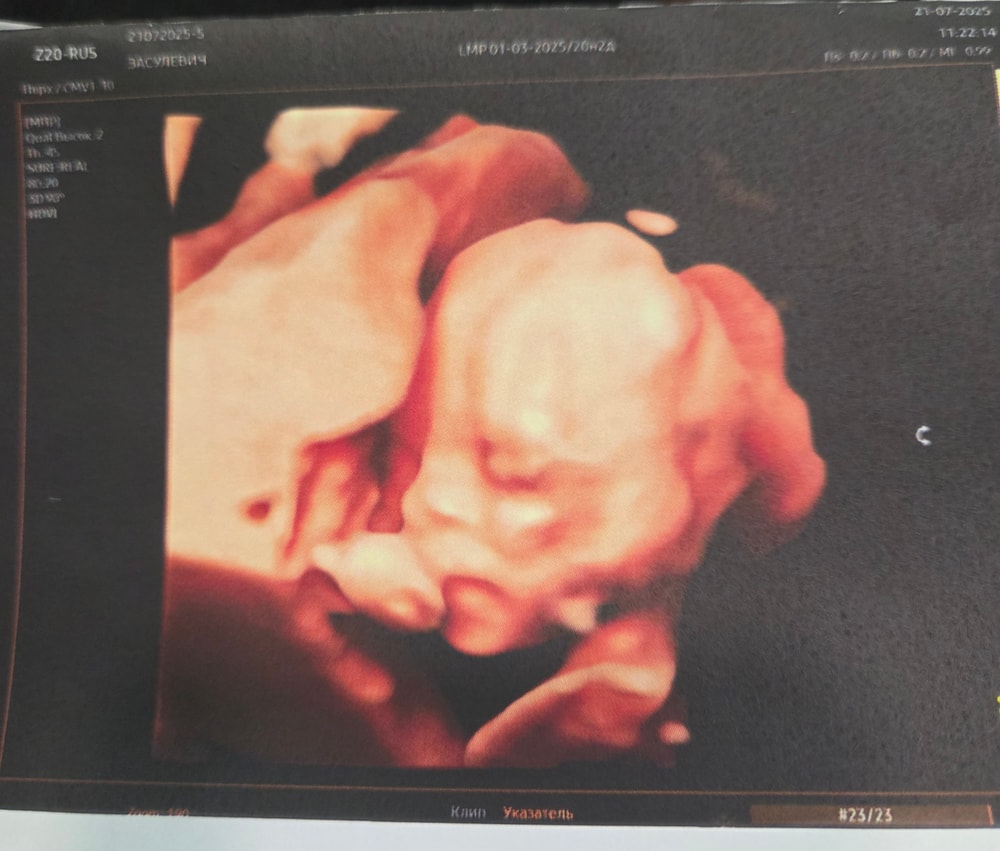

Сегодня 20 недель и 2 дня по М. Девочка наша сидит на попе пока, все все параметры - норма🥰 Идем ровно в срок,на один день больше по узи ,чем по М -20 недель и 3 дня, как и на всех предыдущих узи. Весит целых 364 г , чсс 144. Шейка 39 мм, низкая плацентация моя уже не низкая🥳. В 16 недель плацента была на 10 мм от зева, сейчас уже на 35мм.

Я очень счастлива, расти крошка хорошо и дальше)